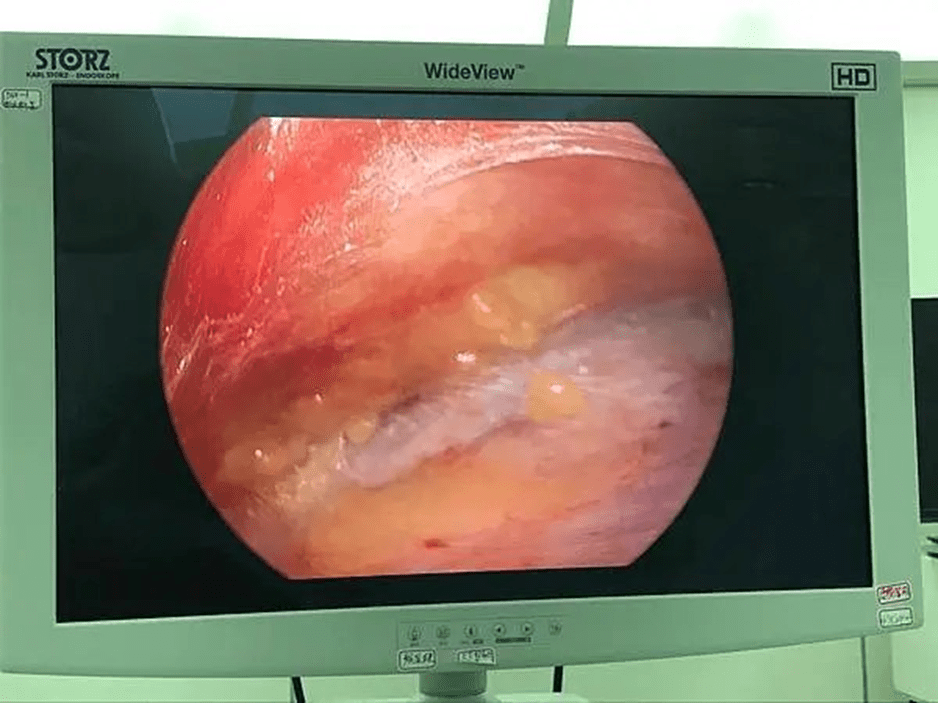

內視鏡下的外觀:

注射填充:https://www.youtube.com/shorts/skjjnkVdwOA